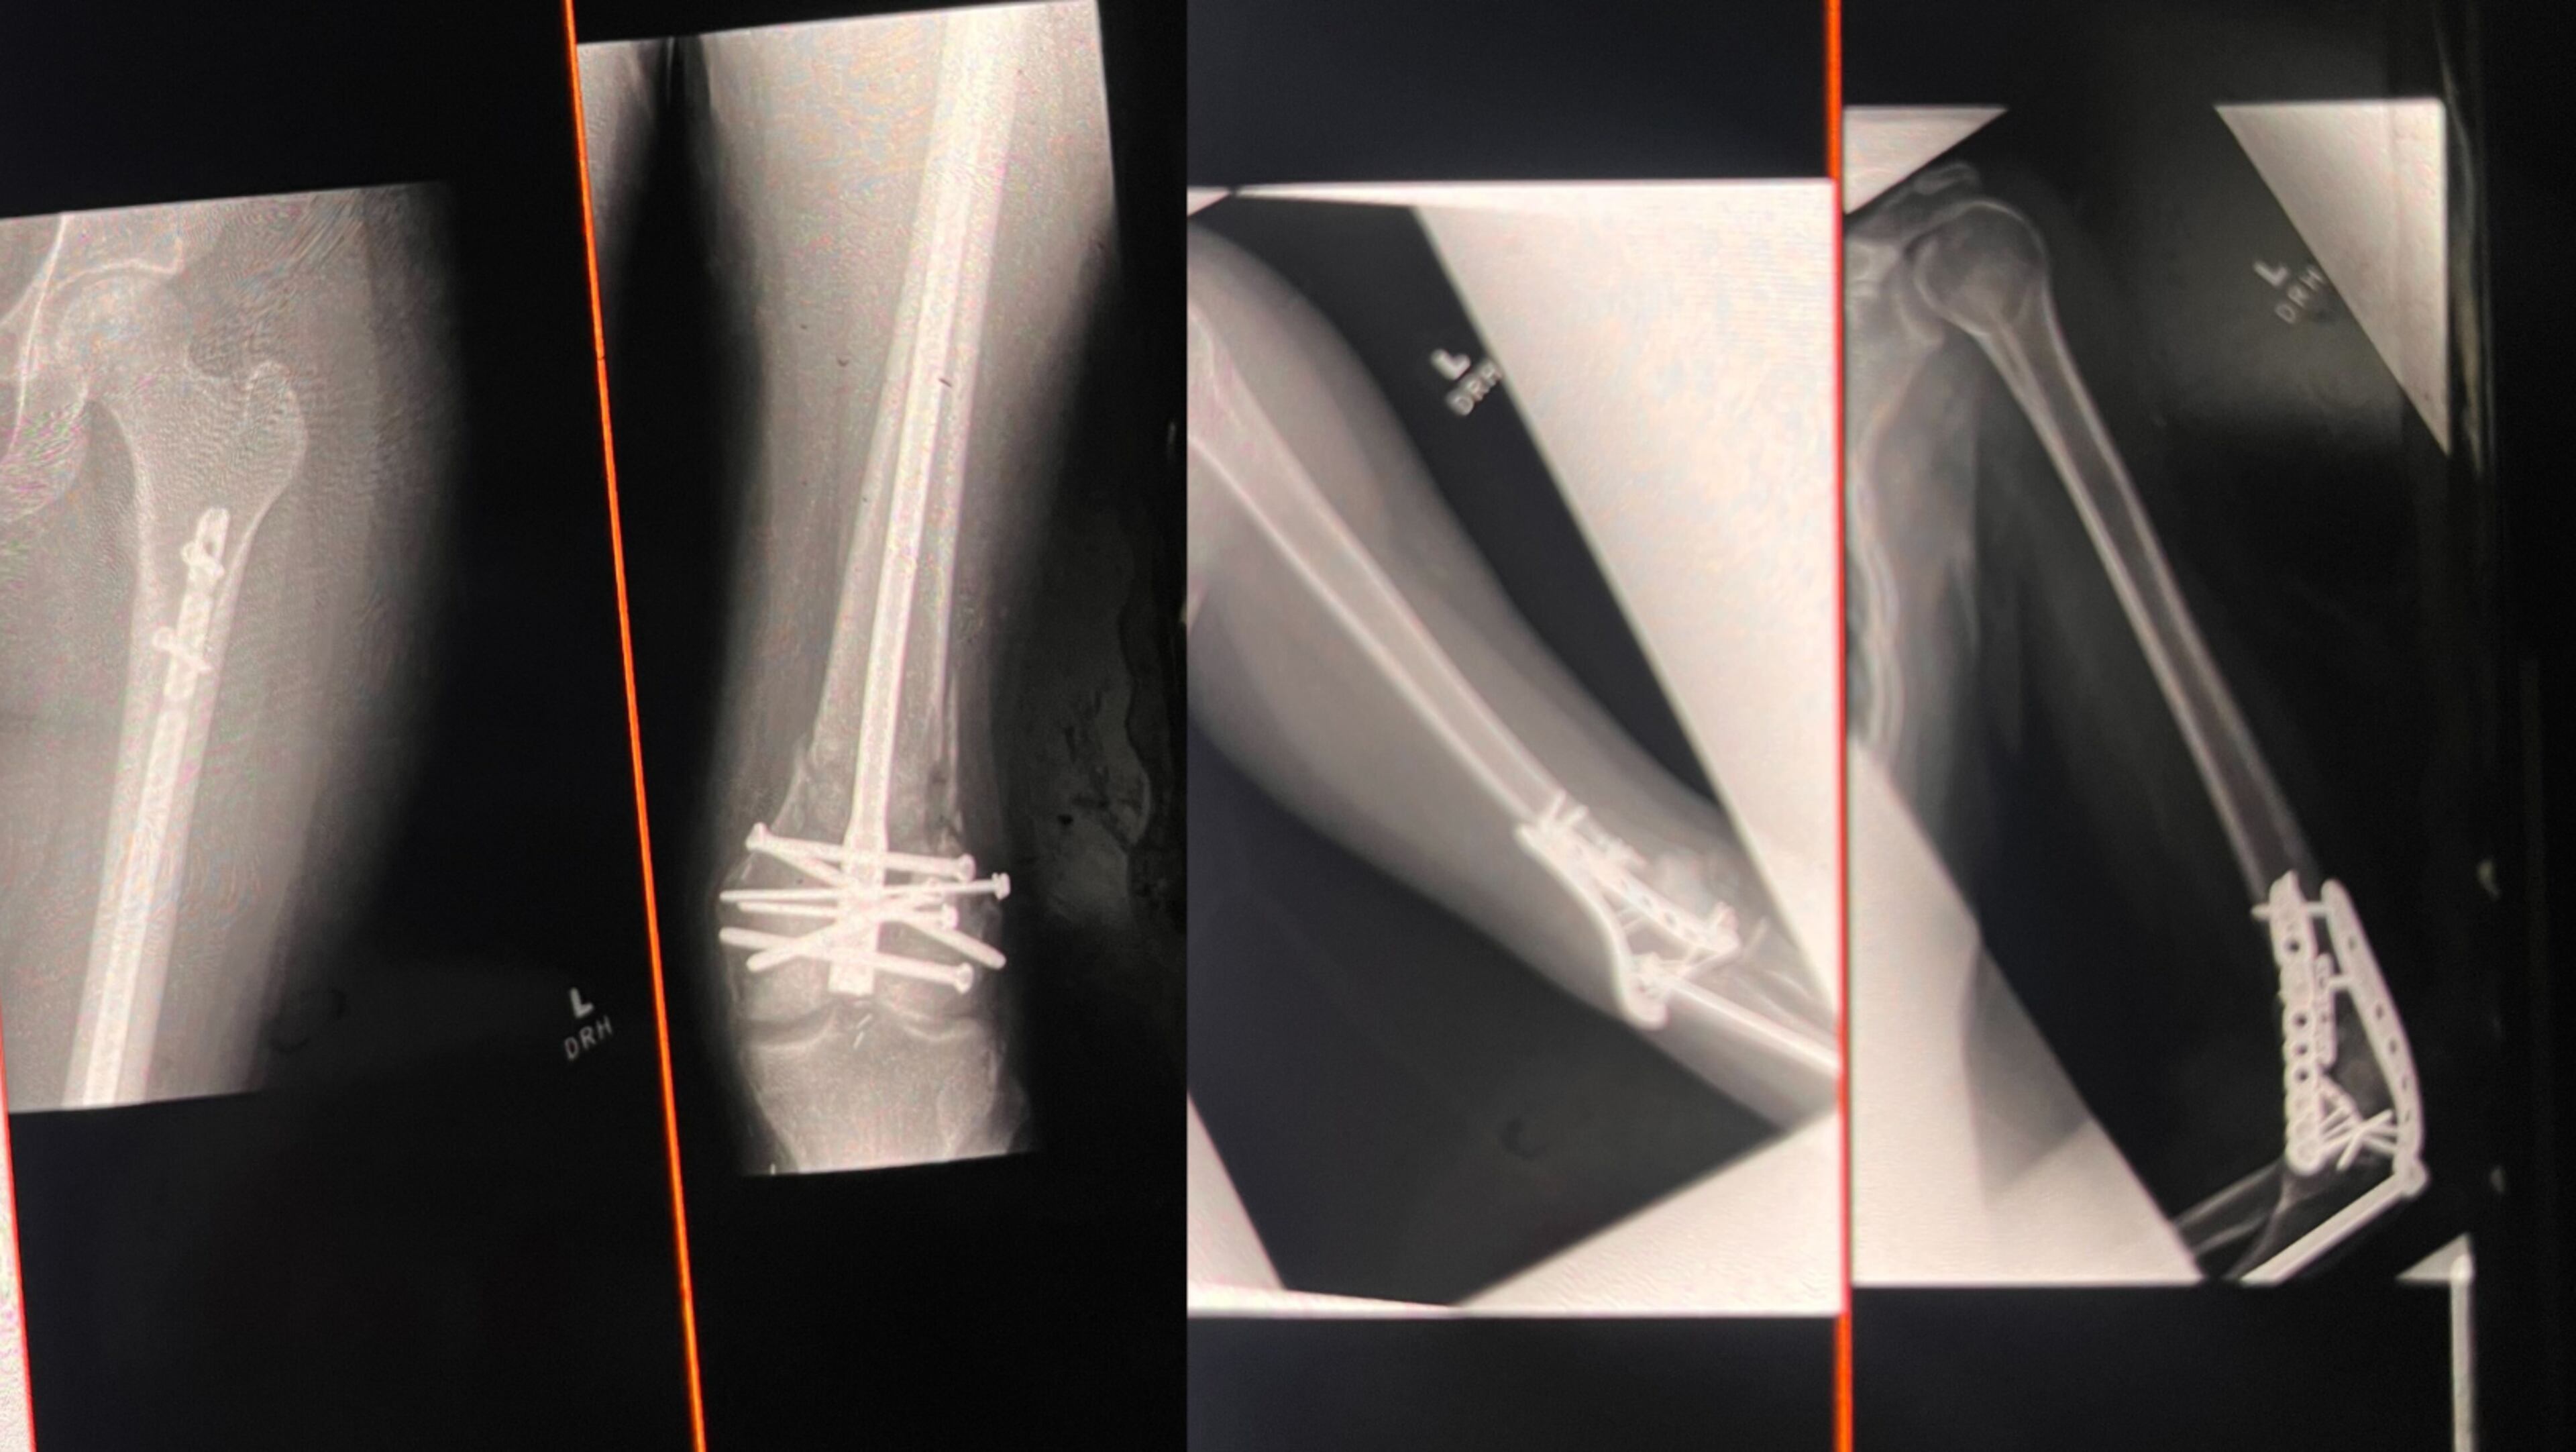

Even the most basic tasks, once effortless, are now arduous. That’s because multiple screws had to be placed in that damaged knee and a metal rod was inserted in her shattered left leg, which narrowly escaped amputation.

The collision’s impact also splintered the 25-year-old’s left arm, fractured her right wrist, neck and nose, and caused her brain to swell and bleed. It forced doctors to place her in a medically-induced coma.

Cassandra “Cassy” Wilhelm, her physical therapist, said during an early March session that Dee’s knee flexion remains limited. Bending it can feel similar to someone sitting on your shoulders and forcing a split. But that’s normal, considering all the hardware in Dee’s body.

“Our goal is that it should be able to normalize. You probably won’t ever get a full range of motion back, but it should be functional,” Wilhelm said, emphasizing that Dee has put more work into her recovery than many of her patients.